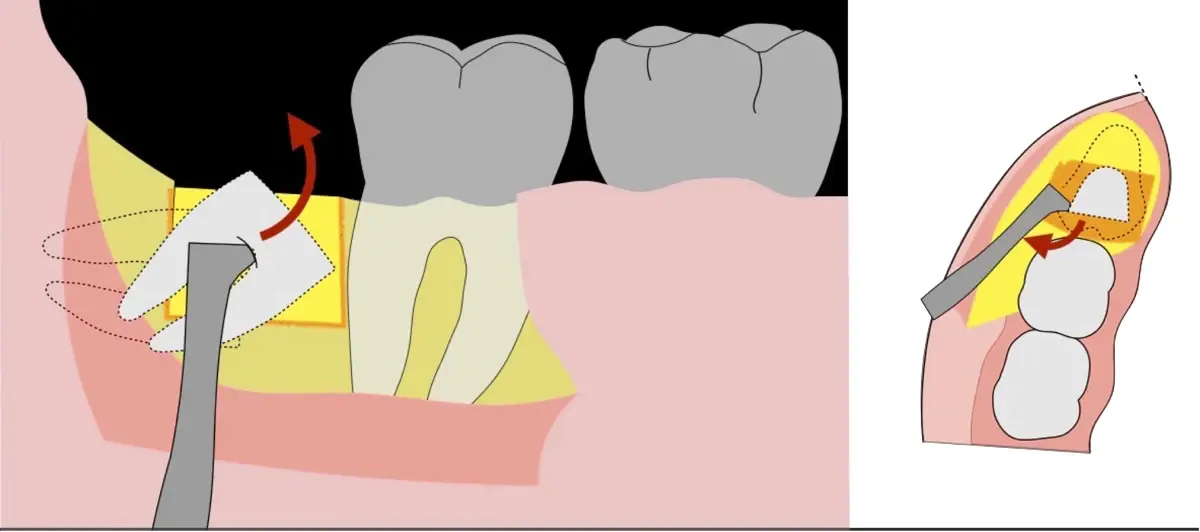

El procedimiento puede variar en su complejidad dependiendo de su ubicación, profundidad, angulación, y la densidad ósea circundante.2 Uno de los pasos más críticos y cruciales en la extracción es la osteotomía previa y concomitante al acceso quirúrgico del diente, para lo cual se utilizan diversos instrumentos como cinceles y martillos, instrumental rotatorio o de corte por ultrasonido.3

En contraste, el instrumento piezoeléctrico utiliza un corte micrométrico que retira un área de superficie mínima de hueso, y reduce el riesgo de termonecrosis marginal en comparación con las fresas rotatorias convencionales.9 Los micromovimientos mejoran la precisión en el corte y el control táctil, y eliminan las macrovibraciones que se producen con los instrumentos rotatorios.10 Su frecuencia de oscilación es la amplitud de 60-200 μm horizontalmente y de 20-60 μm en sentido vertical, lo que es muy inferior en comparación con las micro sierras oscilantes; por lo tanto, proporciona cortes de osteotomía precisos y seguros. Adicionalmente, posee vibraciones ultrasónicas que descomponen el líquido de irrigación en partículas muy pequeñas (fenómeno de cavitación, que produce un efecto hemostático y así reduce la pérdida de sangre), lo que proporciona una visión clara y sin obstáculos del campo quirúrgico11,12.